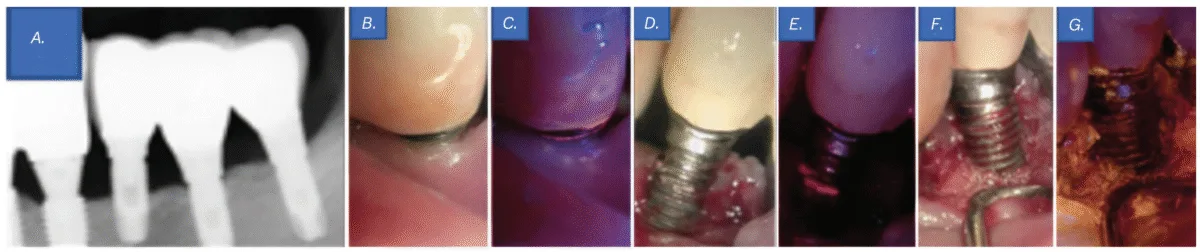

Scientific examination revealed a probing depth of 5–6 mm round implant No. 20, with the implant threads uncovered above the gingiva. Though no vital biofilm attachment was noticed with the bare eye (Determine 4B), QLF revealed the presence of biofilms (Determine 4C). As well as, periapical radiography revealed bone loss round implant No. 20, resulting in a prognosis of peri-implantitis (Determine 4A). Regardless of her dental phobia, the affected person consented to endure flap surgical procedure after an intensive rationalization of the need of actively eradicating components contributing to an infection from the implant floor.

A sulcular incision was constructed from the mesial line angle of No. 21 to the distal line angle of implant No. 19 utilizing #15T and #12 blades. Upon flap elevation, seen biofilm was noticed (Determine 4D), and its presence was confirmed with QLF imaging (Determine 4E). Biofilm elimination was carried out utilizing an ultrasonic scaler (Megagen, Seoul, South Korea), a curette, and a microbrush. Tetracycline was moreover utilized for implant floor decontamination. Subsequent medical and QLF imaging confirmed the profitable elimination of residual biofilm and infectious materials (Determine 4F-4G). The surgical website was then closed utilizing 4-0 absorbable artificial sutures (Coated Vicryl™, Ethicon, Johnson & Johnson, Somerville, New Jersey) with an interrupted suture method.

One week after the flap surgical procedure, the affected person returned for suture elimination. The therapeutic course of was passable, with no irregular findings. At 6-month and 1-year follow-ups, the affected person reported no discomfort, implant floor hygiene had improved in comparison with the pre-treatment situation, and the general oral well being remained secure.